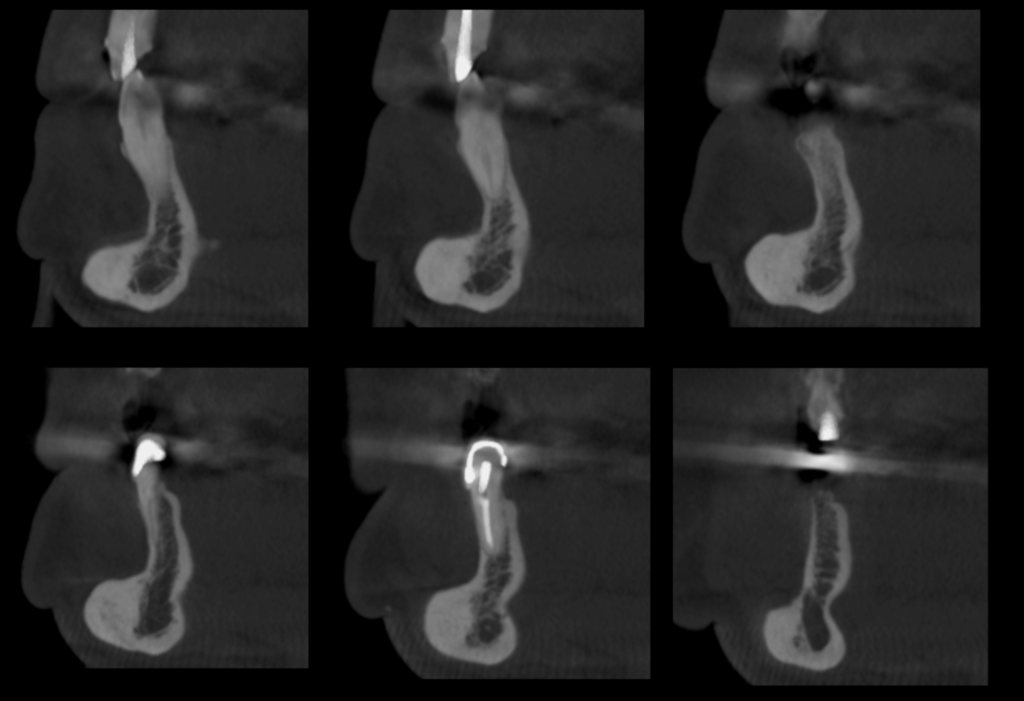

A la evaluación de la tomografía volumétrica de campo 10 x 10 se observa la presencia de la misma imagen hiperdensa a nivel mandibular del lado izquierdo y por vestibular de limites definidos y base pediculada a la altura de las piezas 33 y 34 y muy cerca al conducto dentario inferior compatible con osteoma mandibular.

CORTES SAGITALES